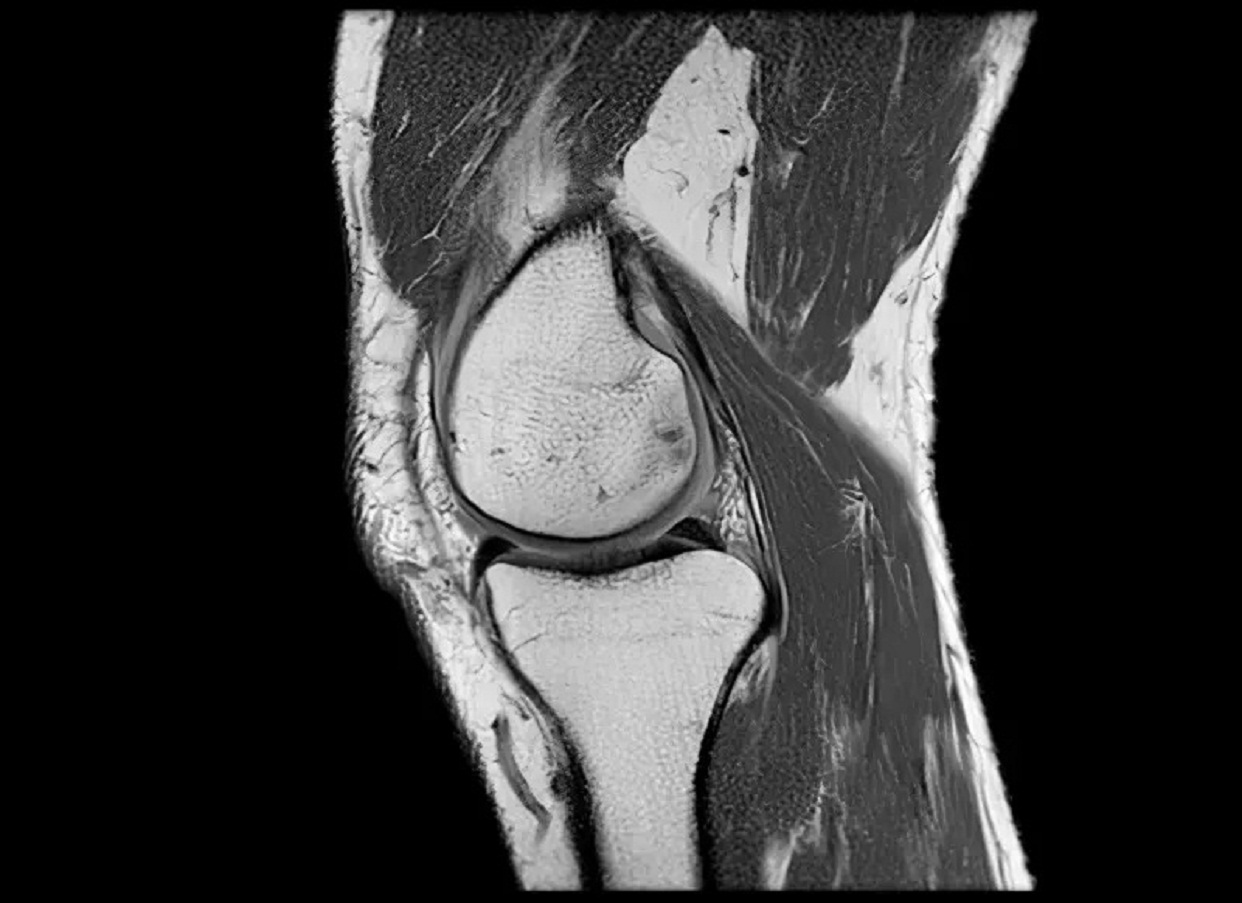

"La rodilla es una de las articulaciones más complejas de todo el cuerpo", le dice a la BBC Anikar Chhabra, un cirujano ortopédico especializado en medicina deportiva de la Clínica Mayo en Phoenix, EE.UU.

Nuestras rodillas dependen especialmente de cuatro grupos de músculos que las rodean: los isquiotibiales, los de los glúteos, los cuádriceps y los músculos de la pantorrilla.

Esos grupos de músculos aportan estabilidad y les dan a las rodillas la capacidad de absorción para poder funcionar.

"Cuando esos músculos no están interactuando y trabajando juntos, la articulación recibe más presión. Ahí es cuando comenzamos a sentir el dolor", señala Chhabra.